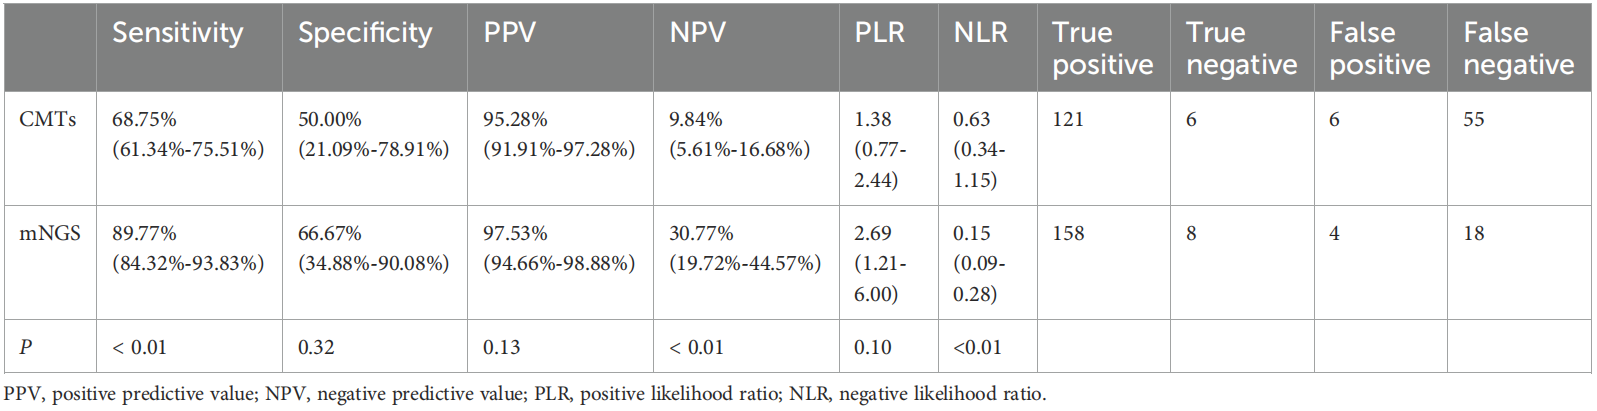

Table 1. Comparison of diagnostic performance.

Table 1. Comparison of diagnostic performance.

The results of the study reveals that mNGS detected pathogens in 86% of cases, significantly outperforming CMTs, which identified pathogens in only 67% of cases. Spectrum of detected pathogens results showed that mNGS identified 59 bacteria, 18 fungi, 14 viruses, and 4 special pathogens while CMTs detected just 28. This enhanced detection capability provides clinicians with a more comprehensive diagnostic tool for pulmonary infections.